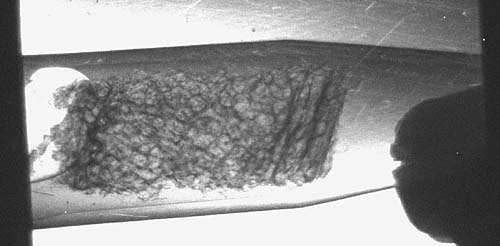

На Курчатовском источнике СИ были проведены исследования биоптатов костной ткани человека, предоставленные Центральным институтом травматологии и ортопедии им.Н.Н.Приорова (ЦИТО). Биоптаты представляют собой небольшие фрагменты, объемом менее одного кубического сантиметра, извлеченные посредством операции из кости и помещенные в формалин. На рис.5 показаны снимки, сделанные методом рефракции (а) и поглощения (б). Видно, что структура кости на рис.5,а проявляется значительно лучше, чем на рисунке 5,б. На верхнем рисунке хорошо виден внешний (кортикальный слой) кости, а также внутренний, который состоит из продольных слоев (трабекул) размером до нескольких сотен микрон. Здесь использование синхротронного излучения приобретает особое значение, потому что другие методы для оценки прочности кости оказываются малоприменимыми. Хотя с помощью электронного микроскопа, дающего очень высокое пространственное разрешение, можно увидеть в кости кристаллы кальцита размером около 1 мкм, но в практической медицине это пока не нашло широкого применения. На синхротронных пучках размеры и ориентацию таких кристаллов удается определять с помощью электронной спектроскопии.

Рис. 5. Изображение биоптата кости человека,

полученное методом рефракции (а) и поглощения (б)

на Курчатовском источнике СИ.